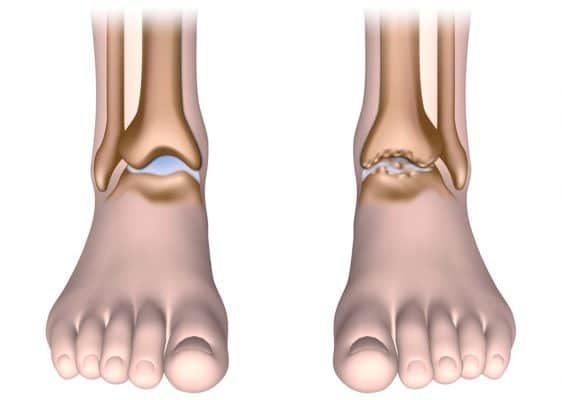

Ankle Osteoarthritis

Ankle OA is less prevalent than other forms of lower limn OA (hip and knee). This is due to the fact that there is relatively good stability in the ankle joint. Usually, the main cause of ankle arthritis is trauma, although secondary arthritis from other medical conditions can occur (e.g. gout, rheumatoid and other inflammatory diseases).